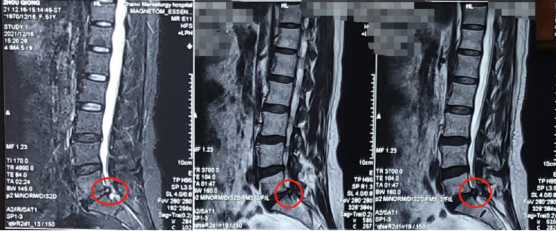

术前影像学资料

熊东主任接诊后,结合赵女士的查体及其他各项检查结果,确诊她为“腰椎间盘突出症(腰5骶1)”。赵女士在腰5骶1处已经出现比较严重的突出且已压迫到神经,而且症状严重影响生活,建议进行椎间孔镜手术微创治疗。